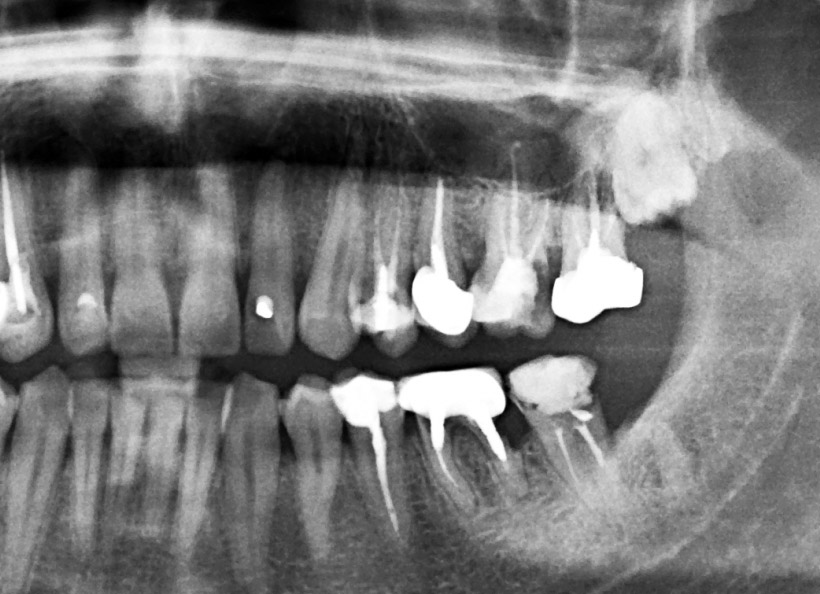

Radiografia digitală panoramică sau Ortopantomografia este radiografia digitală care ne oferă o imagine de ansamblu la toţi dinţii din cavitatea bucală, inclusiv sinusurile maxilare şi aticulaţiile temporo-mandibulare. Este indicată la începerea unui tratament stomatologic pentru a vedea zonele mai greu accesibile ale dinţilori, retracţiile osoase, existenţa şi adâncimea pungilor parodontale, existenţa dinţilor incluşi, etc.

Radiografia digitală panoramică O.P.T. pentru sinusurile maxilare